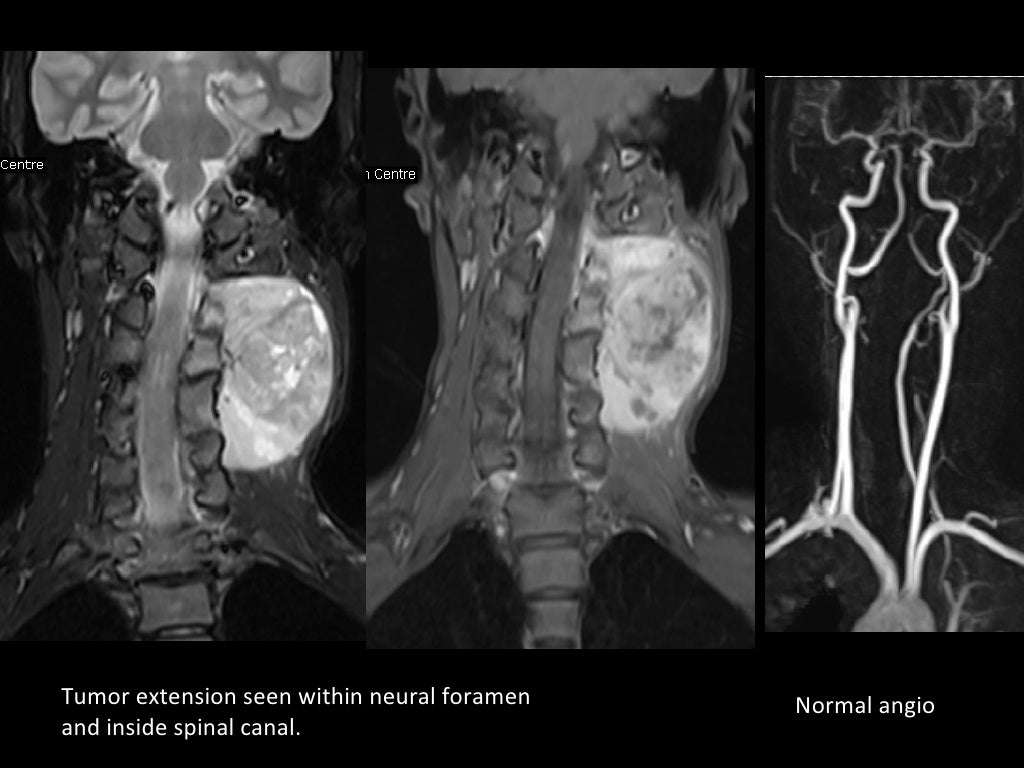

From www.slideshare.net

MRI in neck imaging Arthritis In Neck Mri It also explores the various. if your doctor suspects you have a type of arthritis, such as osteoarthritis, he or she may use a magnetic resonance imaging (mri). The discs may naturally dry. Healthcare providers sometimes call it. the article describes the symptoms, causes, and diagnosis of neck arthritis. Spondylosis is when parts of your spine begin to. Arthritis In Neck Mri.

MRI in neck imaging Arthritis In Neck Mri The discs may naturally dry. if your doctor suspects you have a type of arthritis, such as osteoarthritis, he or she may use a magnetic resonance imaging (mri). cervical refers to seven stacked bones (vertebrae) in your neck. Healthcare providers sometimes call it. the article describes the symptoms, causes, and diagnosis of neck arthritis. Two of the. Arthritis In Neck Mri.